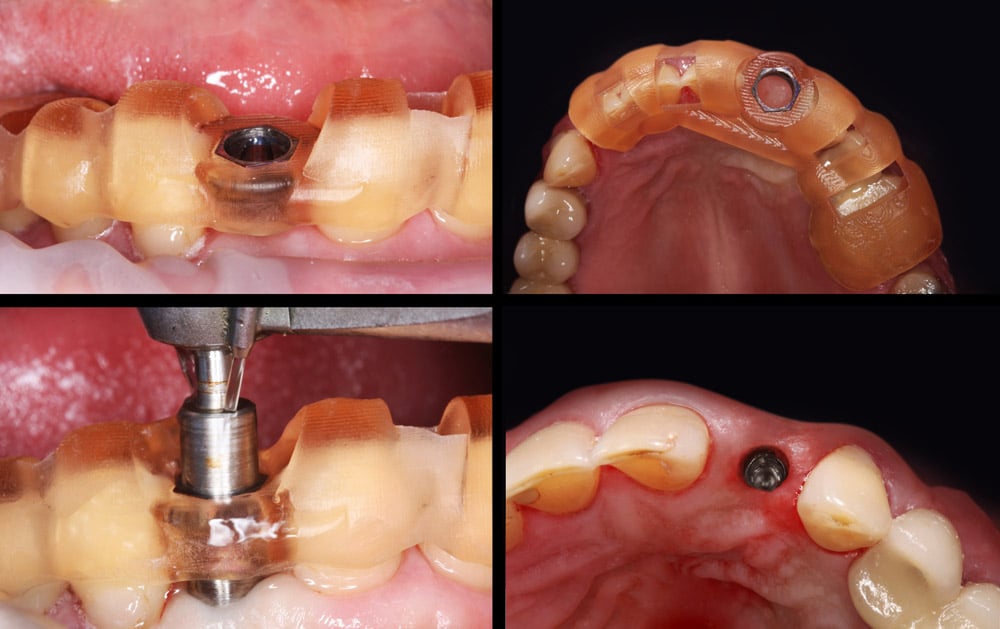

Krok drugi – cyfrowa wizualizacja opcji terapeutycznych i przygotowanie pacjenta do zabiegu.

Krok trzeci – szybki i bezbolesny zabieg.

– precyzja: umieszczenie implantów idealnie w centrum zaprojektowanej korony.

– bezpieczeństwo: ten zabieg pozwala oszczędzić tkankę dziąsłową i zabezpieczyć kość otaczającą przed jej nadmierną utratą i skaleczeniem.

– oszczędność czasu: pacjent zostaje na fotelu nie dłużej niż 15 min w porównaniu z zabiegiem konwencjonalnym, który trwa 1,5 godziny!!!